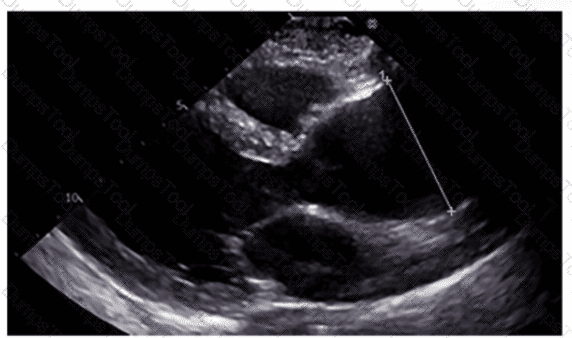

Which sonographic views allow visualization of a patent ductus arteriosus (PDA)?